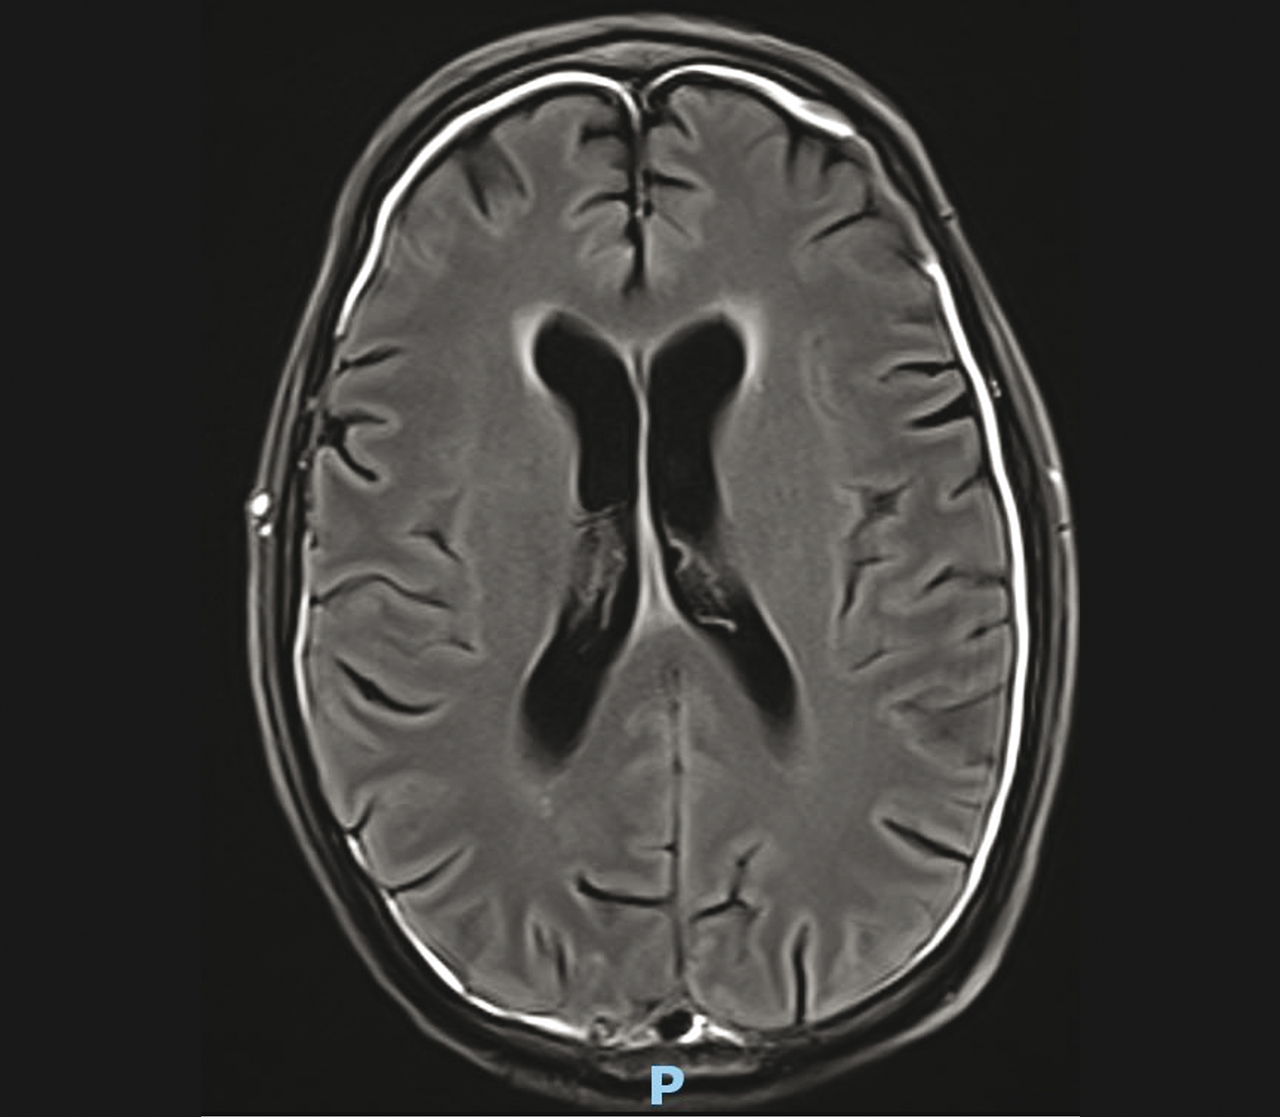

Homme de 56 ans , vivant dans des conditions précaires, tabagisme de 45 paquets-année, se plaignant de céphalées et ayant des troubles du comportement. Quel est votre diagnostic ? Hématome sous-dural Méningiome Pachyméningite tuberculeuse Leptoméningite tuberculeuse Méningite carcinomateuse OK Valider mes réponses